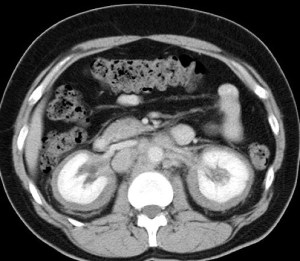

CASO 2: Paciente de 68 años con dolor en flanco izquierdo, fiebre y malestar general. A la exploración existe enrojecimiento de la piel con sensación de masa palpable y puño percusión muy positiva.

El paciente es alégrico al Iodo. Se realiza TC sin contraste para ampliar estudio.

Todos estos hallazgos están en relación con una Pielonefritis Xantunogranulomatosa que afecta al riñón derecho junto con una colección que ha fistulizado a región lumbar.

- Pielonefritis Xantunogranulomatosa.

- Es una forma infrecuente de pielonefritis crónica, de origen obstructivo, caracterizada por la formación de un absceso granulomatoso que puede extenderse al EPR-, severa destrucción renal y un cuadro clínico de fiebre, malestar general, dolor en el flanco y masa renal, a veces palpable.

- En placa simple podía verse un masa que renal con o sin borramiento de la línea del psoas. En ecografía, cálculos y aumento del tamaño renal en la forma difusa con múltiples áreas anecoicas correspondientes a las colecciones purulentas.

- Los hallazgos en TC pueden ser:

- Uni o bilateralidad de la lesión.

- Afección difusa o localizado.

- Litiasis de tipo coraliforme, calcificaciones intraparenquimatosas.

- Aumento difuso del tamaño renal.

- Áreas hipodensas o hipoecogénicas dentro de la lesión renal debidas a cálices dilatados, abscesos o áreas de necrosis parenquimatosa.

- Pobre o nula eliminación del medio de contraste en el riñón afectado.

- Compromiso inflamatorio que excede los límites del riñón y genera colecciones periféricas o extensión hacia vísceras vecinas.